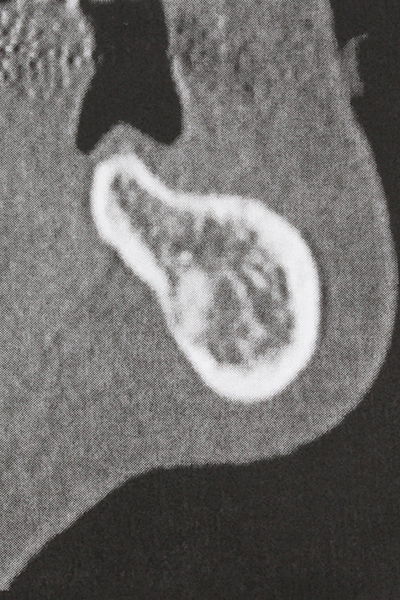

La preparación de la ventana lateral en la elevación del suelo del seno maxilar representa un enorme reto, sobre todo para profesionales de la implantalogía que tienen poca experiencia en técnicas quirúrgicas. Retirar la cobertura ósea del seno maxilar sin provocar daños en la membrana de Schneider es tan solo una parte de la operación; tras crear un acceso suficiente, es preciso movilizar con cuidado la mucosa del seno maxilar a fin de dejar espacio para el material o los implantes que vayan a incorporarse. En esta aplicación la cirugía piezoeléctrica resulta útil en dos sentidos: por un lado, el uso de insertos diamantados permite realizar una retirada selectiva del hueso y, si se actúa con cuidado, la membrana permanece intacta, y por otro lado, las frecuencias de ultrasonidos favorecen también un desprendimiento sin problemas de la membrana, pues se transfieren al espacio comprendido entre la mucosa y el suelo del seno maxilar gracias al uso de piezas romas especiales (Cassetta, Ricci et al. 2012, Pereira, Gealh et al. 2014) (Rickert, Vissink et al. 2013). De este modo, no es de extrañar los trabajos publicados en la actualidad sobre la técnica de elevación del suelo del seno maxilar mediante la técnica de Caldwell-Luc con instrumentos piezoeléctricos (Wallace, Tarnow et al. 2012).

En la cirugía del seno maxilar surgen otros campos de aplicación: En este punto, tras la preparación concéntrica de una tapa ósea de la pared del seno maxilar (que suele tener forma trapezoidal), es posible eliminar patologías y cuerpos extraños del seno maxilar. La tapa ósea se repone después de finalizar la parte intra-antral de la operación y se asegura frente a una posible dislocación mediante cuñas o suturas adaptables.